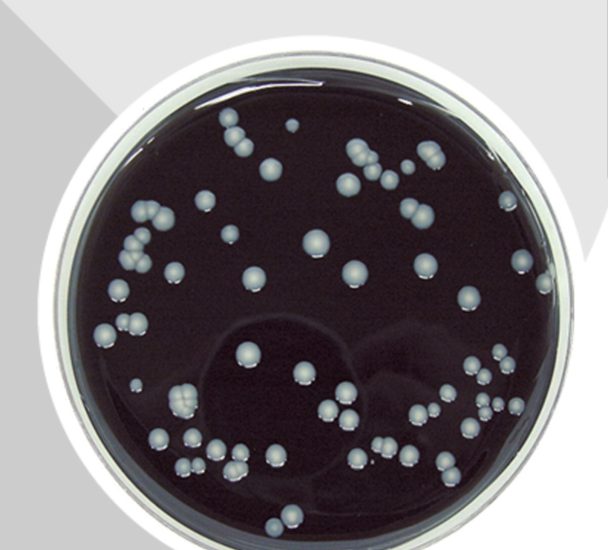

Për të konstatuar tkurrjen e bakterit ka disa teste specifike si testi i antitrupave fluoreshente , kultura e pështymës, testi i shpejtë i antigjenit urinar. Dhe pastaj përsëri testet e reaksionit zinxhir polimerazë, të quajtur PCR. Kësaj i shtohet edhe ekografia e gjoksit e cila konfirmon sëmundjen. Duke qenë se ky është një infeksion bakterial, ai trajtohet me antibakterialë në gjendjen fillestare.